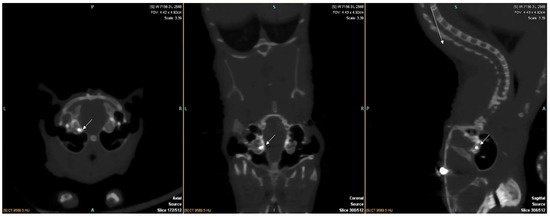

2.2. Cochlear Implant Surgery

2.3. Tissue Preparation